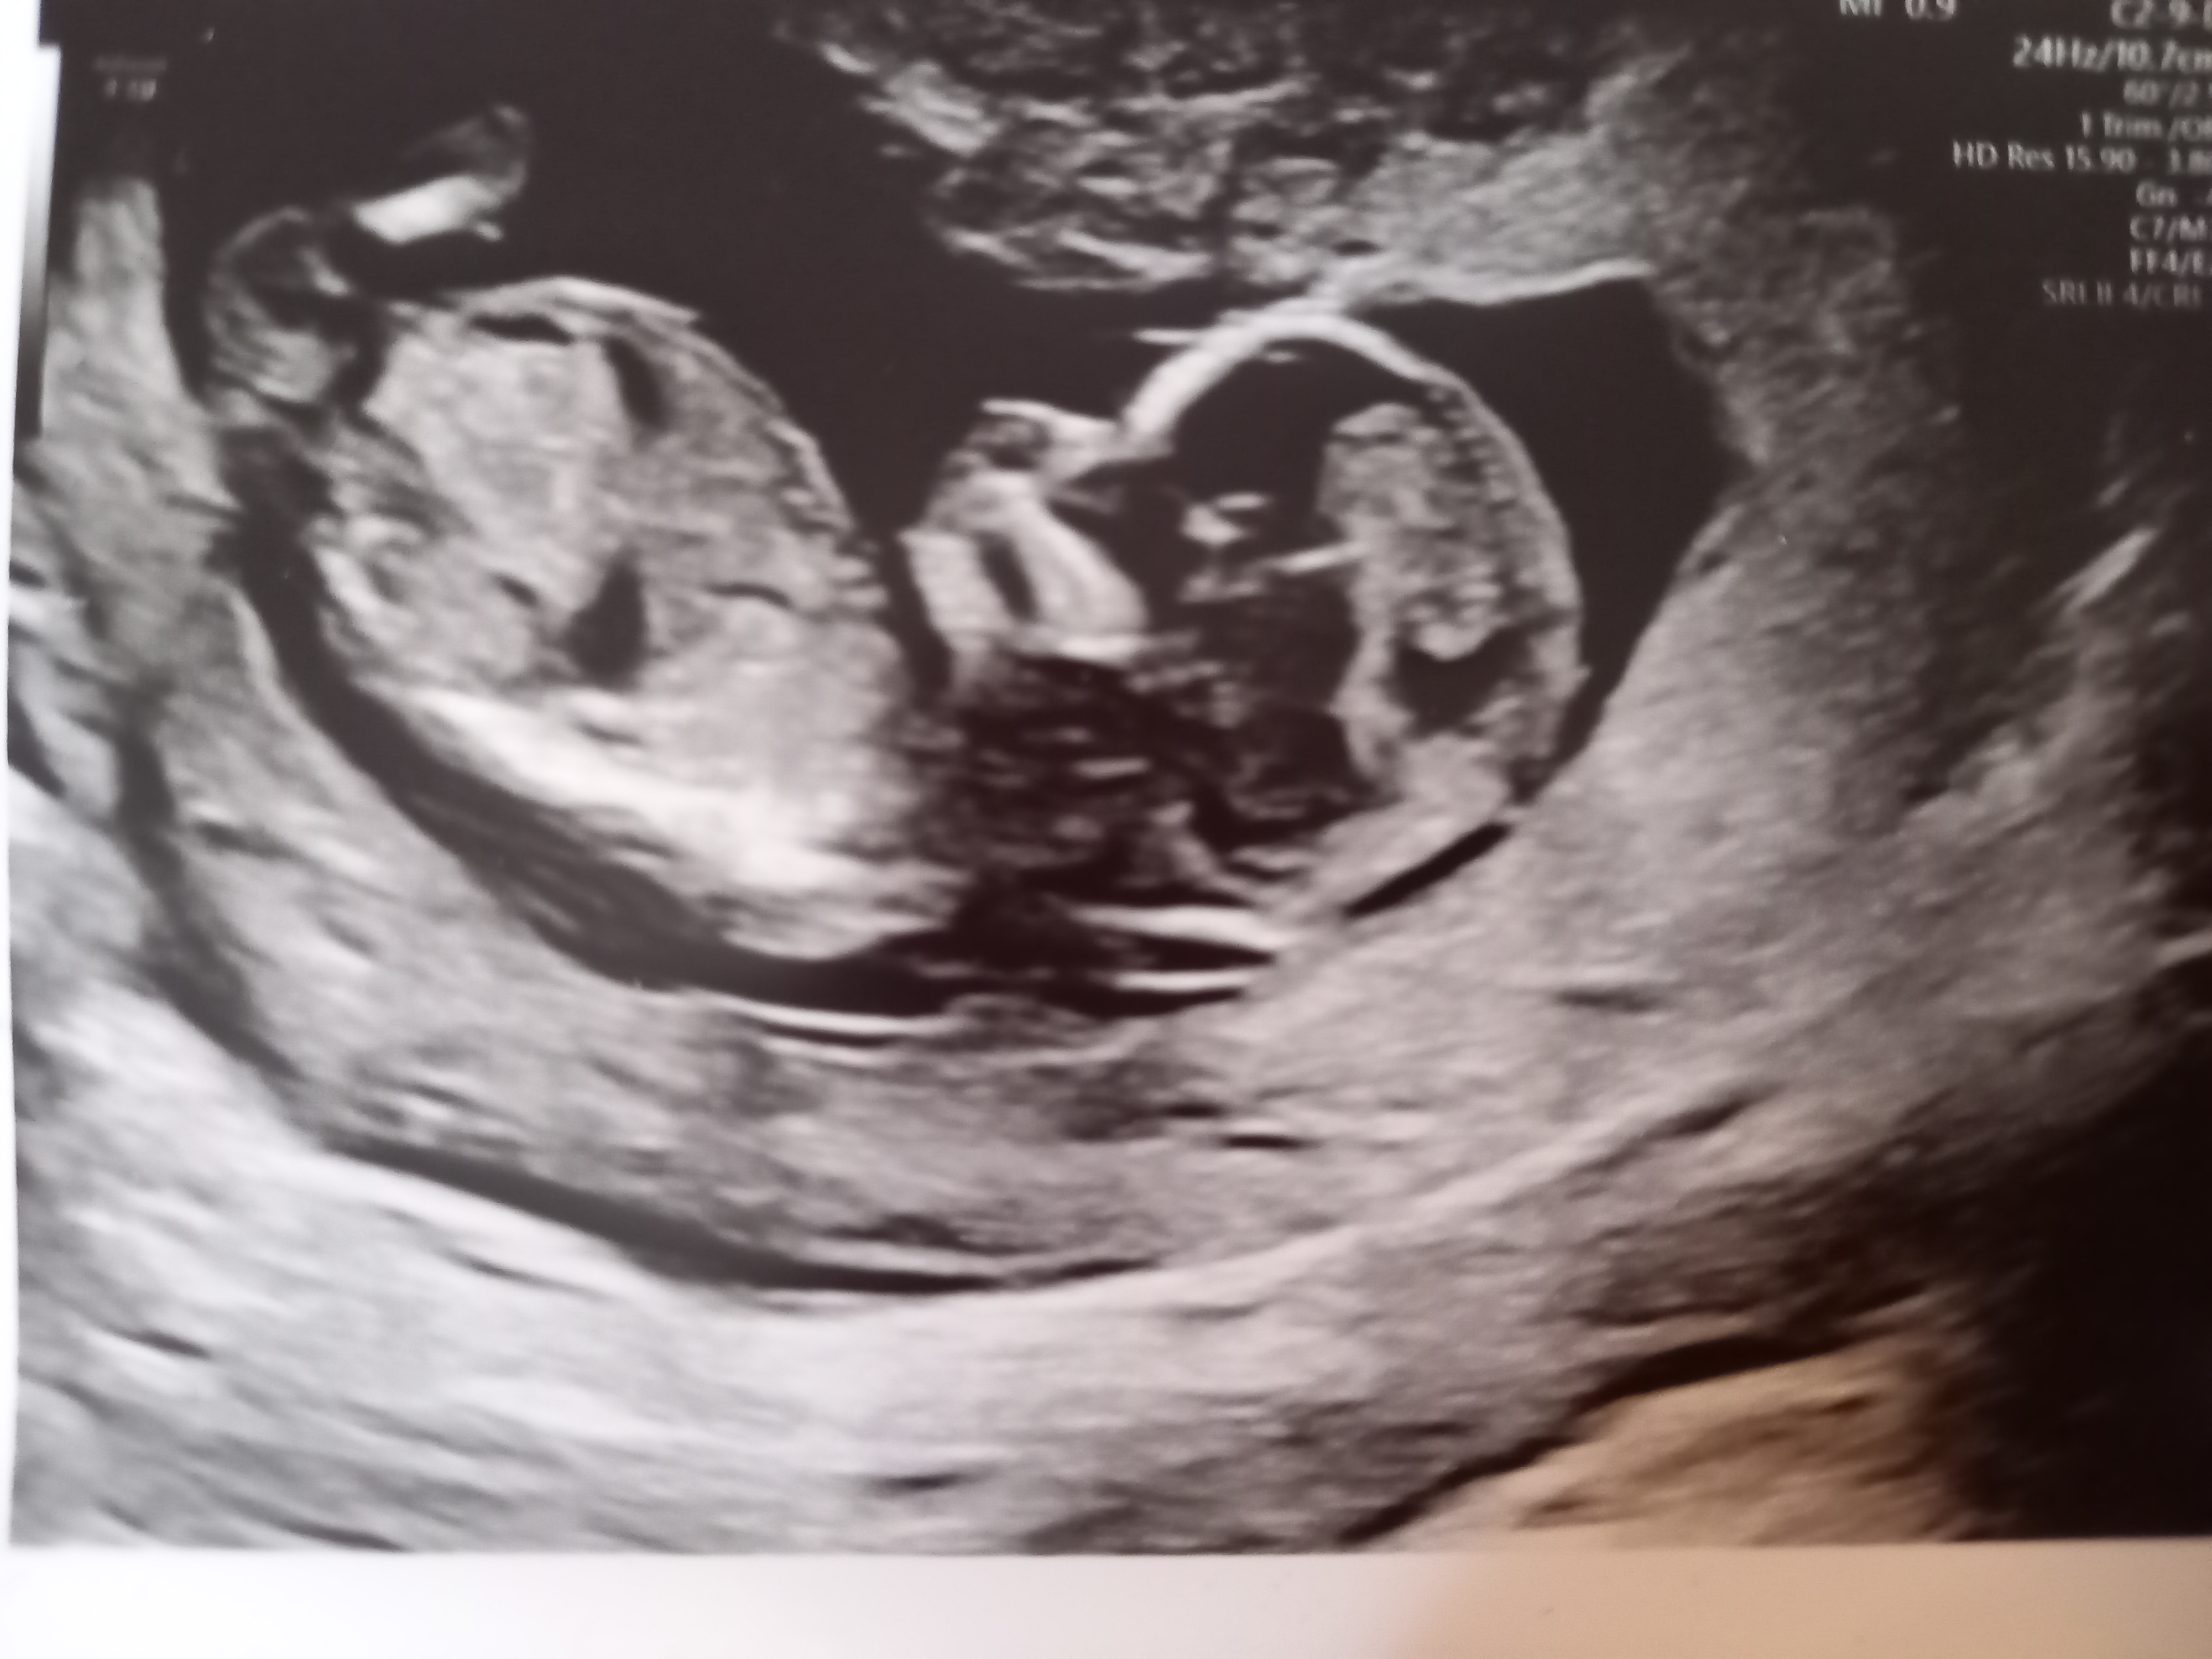

SÅ kommer vel det gøyeste, som alle har ventet på: ultralyden!

De var to stykker, hun som gjorde det meste virket som hun var under opplæring, de har jo nettopp begynt med TUL ca. uke 12 for alle nå for en måned siden. Med én gang hun satte den dingsen på magen, så vi med én gang at der var det en liten baby som bevegde på seg!

Jeg ble målt ca. like langt som jeg mener jeg er, og alt av organer osv. var akkurat som det skulle være

Vis vedlegget 389512 Vis vedlegget 389513 Vis vedlegget 389514